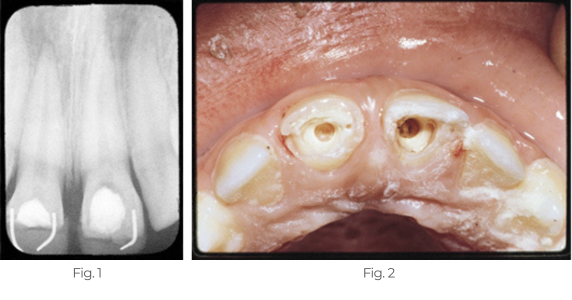

Dentin Bridge Formation

Case 1

This histological section stained with H & E shows new dentin bridge formation two months following pulpal curettage and treatment with Pulpdent Paste.

Case 2

The patient presented in pain with fractured upper central incisors and exposed pulps. Pulpotomies were performed using Pulpdent Paste as the pulpal dressing, which was sealed in place with zinc phosphate cement. Composite restorations were placed using pins for retention. One year after the pulpotomies, the patient returned for more esthetic composite restorations.

A radiograph taken after one-year shows two new dense dentin bridges with composites held in place with pins.

Fig. 1; This is a rare photograph of the new dentin bridges after removal of the composite, pins and zinc phosphate cement.

Fig. 2: Multi-Cal can also be used for dentin bridge formation in direct pulp capping, pulpal curettage and vital calcium hydroxide pulpotomy procedures.